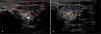

A female infant aged 2 months presented with progressive swelling in the left preauricular region since birth. There was a blueish discoloration this area. There were no additional clinical or laboratory findings, such as fever or malnutrition. A parotid gland ultrasound (US) scan was performed with a preliminary diagnosis of acute parotitis and infantile haemangioma. The scan showed significant enlargement and diffuse hypervascularity in the left parotid gland. The right parotid gland was normal (Fig. 1). The patient received a diagnosis of infantile haemangioma, as there was no evidence of infection, and treatment with propranolol was initiated. At the 3-month follow-up, the size and vascularisation of the haemangioma had decreased (Fig. 2).